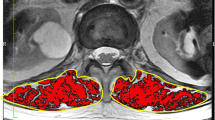

At the time of enrollment and at the 3- and 6-month follow-ups, the patients were examined using plain radiography and spine MRI. MRI was carried out with 1.5-T MRI scanners. The multifidus (MF) and erector spinae (ES) including the longissimus and iliocostalis were identified as the medial-to-lateral PVMs. The border between the MF and ES was scouted from the mammillary processes [20]. The cross-sectional area (CSA) was calculated by the average of the left and right PVM regions of interest of the axial T2-weighted image. The fat signal fraction (FSF) was calculated as the ratio of signal fat/CSA × 100. The CSA and FSF at the superior endplate of L3 were measured using a software program (Horos, version 2.0.1, Horos Project). PVM decrease was defined as > 1 standard deviation (SD) decrease in the CSA (0.9 cm2) or > 1 SD increase in the FSF (5.7%) at the 6-month follow-up compared with the values at the time of injury.

Regarding the trend of the CSA and FSF, there were no trends in the CSA of ES, MF, and total PVM (Table 1). On the other hand, the FSF in both ES and MF showed an increasing tendency from 42.3% ± 7.8% and 53.0% ± 8.9% to 44.2% ± 8.3% and 55.4% ± 9.3%, respectively, for 6 months (p = 0.078 and 0.055, respectively). The FSF of total PVM showed a significant increase from 47.7 to 49.8% for the period (p = 0.033). The mean change in the CSA and FSF of total PVM was − 0.2 cm2 ± 0.6 cm2 and 2.1% ± 3.6%, respectively. There were 30 patients with PVM decrease at the 6-month follow-up.

The results of the multivariate logistic regression model are listed in Table 5. Compared with the status of “dependent or requires assistance to leave home,” patients with the status of “bedridden or nearly bedridden” at the 3-month follow-up displayed a fourfold increase of the risk for PVM decrease (OR = 5.35; 95% CI, 1.23–23.34). Patients who had delayed union at 6-month follow-up also increased the OR for PVM decrease (OR = 4.12; 95% CI, 1.16–14.71). The admission significantly reduced the risk for PVM decrease (OR = 0.24; 95% CI, 0.06–0.97). VAS of back pain at the 6-month follow-up was associated with PVM decrease (OR = 1.24; 95% CI, 1.02–1.49). A typical case was shown in supplementary figure. The case showed the increase of the FSF at 3- and 6-month follow-up.